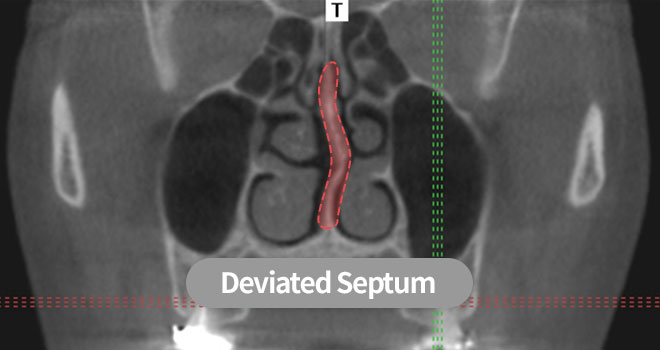

Nose has a very important function of breathing. TS aims to maintain good nasal breathing through functionally comfortable surgery by examining the space inside the nose and the nasal septum shape.

BeforeBlocked nose due to deviated septum

AfterWidened air-way by improving deviated septum